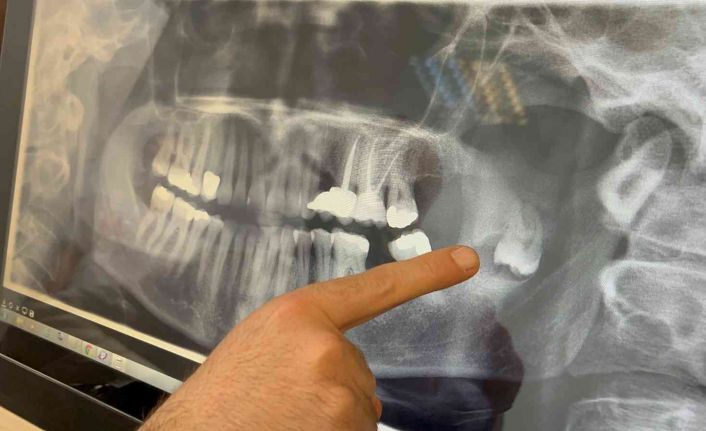

Sevan Kazak Ertural, yaklaşık 12 yıl önce bir panoramik röntgende fark ettikleri gömülü dişin çene kemiğindeki ramus bölgesinde yer aldığını söyledi. Bir zararı olmadığı ve riskli bölgede olduğu için bu dişi almaya kimsenin yanaşmadığını belirten Ertural, “Daha sonrasında dişin kistleştiğini ve çene kemiğime zarar verdiğini fark ettik. Çene kemiğimin bir kısmını eritmişti. Tekrar yaptığım başvurularımda kalıcı yüz felci olabileceğini, çenemin kırılabileceğini, sinire çok yakın olduğu için kolayca müdahale edilemeyeceğini söylediler. Bu sene içinde Ömür Hoca ile tanıştım, buraya başvurdum. Sağ olsun beni çok cesaretlendirdi, bütün riskleri anlattı. Korkmamam gerektiğini söyledi ve ondan güven alarak burada ameliyat olmaya karar verdim” dedi.

Süreç hakkında bilgi veren Doç. Dr. Ömür Dereci, hastanın yaklaşık birkaç ay önce çenesinde ciddi bir ağrı şikâyetiyle kliniğe başvurduğunu kaydetti. Doç. Dr. Dereci, “Yapılan incelemelerde çenesinde tamamen pozisyonu bozuk, ters dönmüş ve yukarı doğru çenenin derin taraflarına doğru ilerlemiş bir diş ve bu dişle ilişkili bir kiste rastladık. Cerrahi bir operasyonla hastamız tamamen uyutularak ameliyat edildi ve bu diş ve ilişkili kist buradan tamamen çıkarıldı. Yapılan muayene ve kontrollerde gayet iyi iyileştiği gözlendi” diye anlattı.